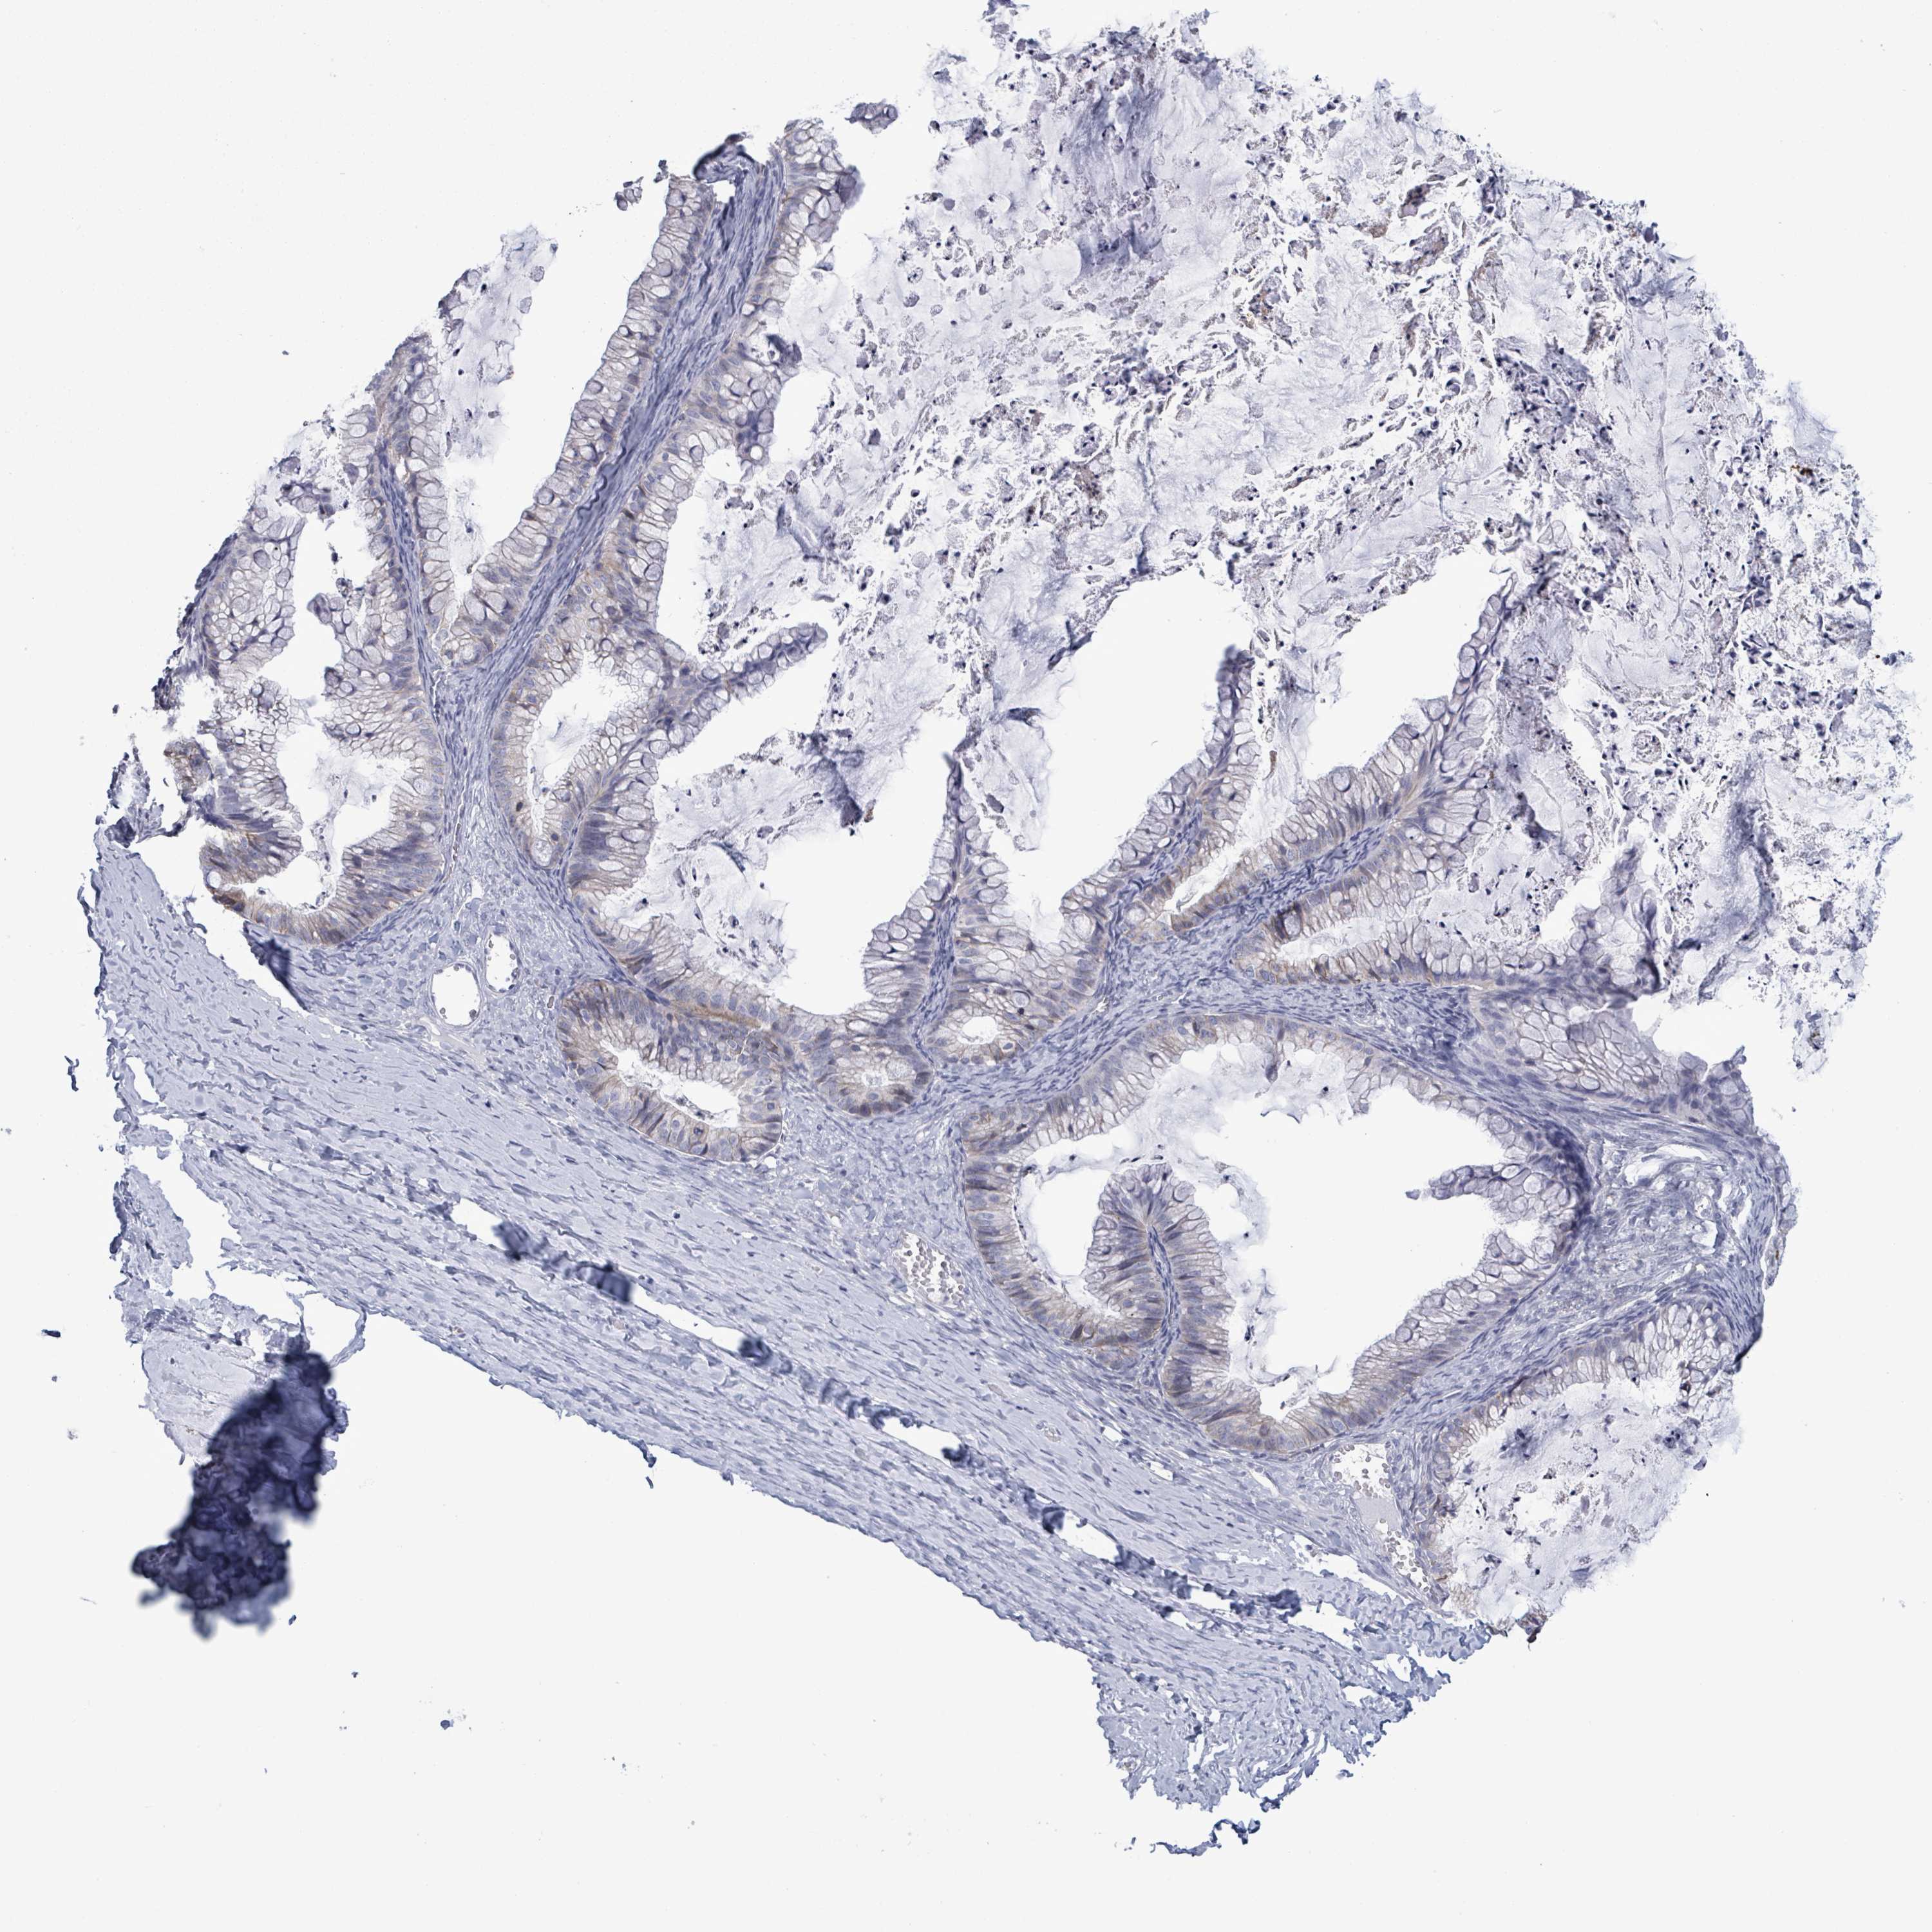

OVARIAN CANCER - Protein expressioni

A mouse-over function shows sample information and annotation data. Click on an image to view it in a full screen mode. Samples can be filtered based on level of antibody staining by selecting one or several of the following categories: high, medium, low and not detected. The assay and annotation is described here.

Note that samples used for immunohistochemistry by the Human Protein Atlas do not correspond to samples in the TCGA dataset.

Antibody stainingi

Antibody staining in the annotated cell types in the current human tissue is reported as not detected, low, medium, or high, based on conventional immunohistochemistry profiling in selected tissues. This score is based on the combination of the staining intensity and fraction of stained cells.

Each image is clickable and will lead to virtual microscopy that enables deeper exploration of all samples and also displays staining intensity scores, fraction scores and subcellular localization as well as patient and tissue information for each sample.

Antibody HPA036048

Antibody CAB002427

Staining

High

Medium

Low

Not detected

Intensity

Strong

Moderate

Weak

Negative

Quantity

>75%

75%-25%

<25%

None

Location

Nuclear

Cytoplasmic/membranous

Cytoplasmic/membranous,nuclear

Cystadenocarcinoma, serous, NOS

Carcinoma, NOS

Cystadenocarcinoma, mucinous, NOS

Carcinoma, endometroid